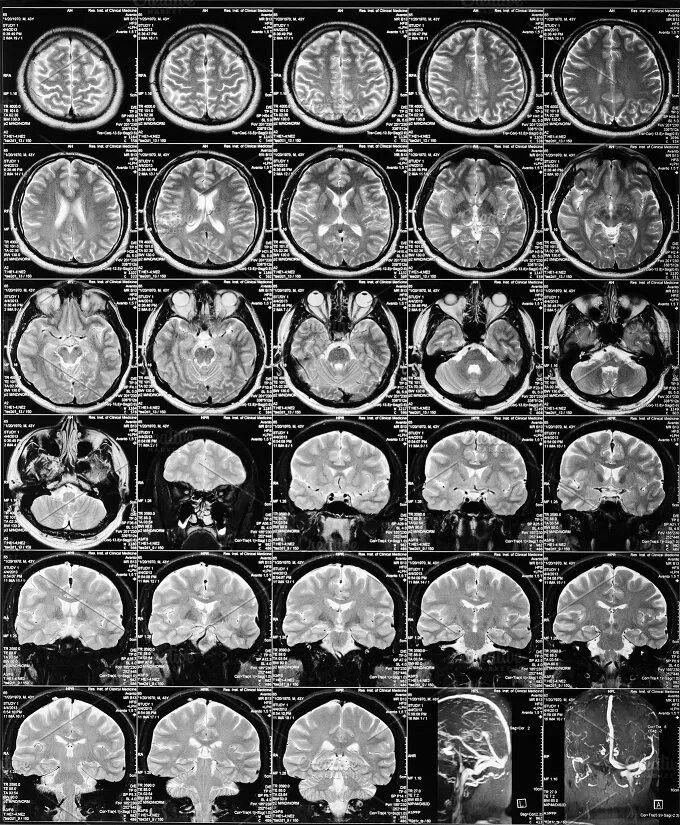

Можно заменить кт на мрт